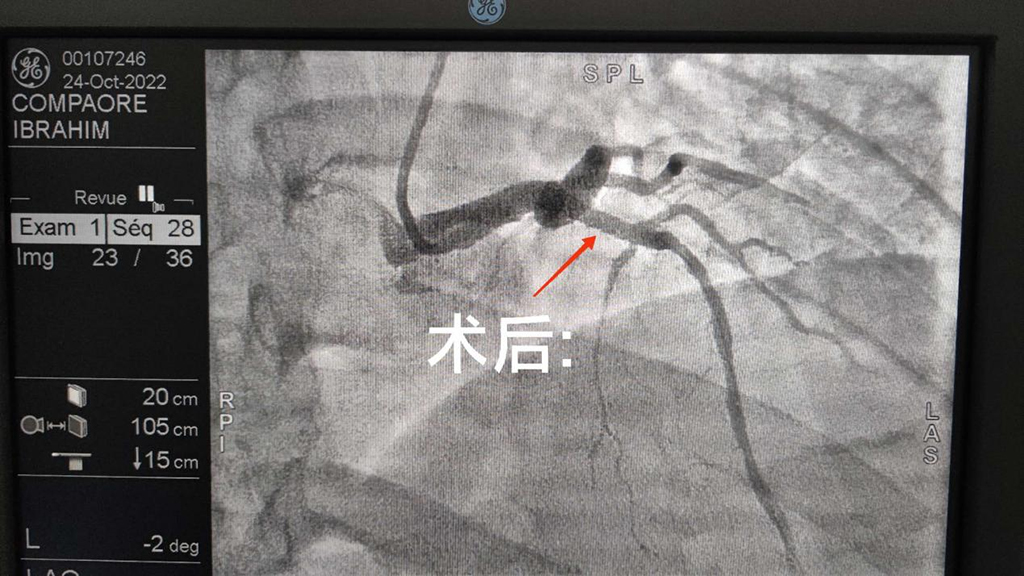

新一批队员到来之后,我很快融入集体,继续开展工作,运用自己的专业知识服务当地患者。由于当地气候等多方面原因,用于手术的DSA机器出现故障,历经重重困难,于近日维修完毕后,立即投入临床工作。最近在门诊接诊两名患者,都因间断胸前区疼痛,胸闷,来院就诊;结合患者心电图及临床症状,考虑冠心病可能;在权衡手术治疗和药物保守疗法的风险和利弊以后,建议患者行冠脉造影检查,安排患者住院治疗。其中一位患者行冠状动脉造影检查:提示前降支重度狭窄,给予前降支植入一枚支架,和当地医生一起完成手术:手术过程中,由于语言的差异,有时会用上“肢体语言”,用手比划。大家克服困难,齐心协力,共同完成手术。